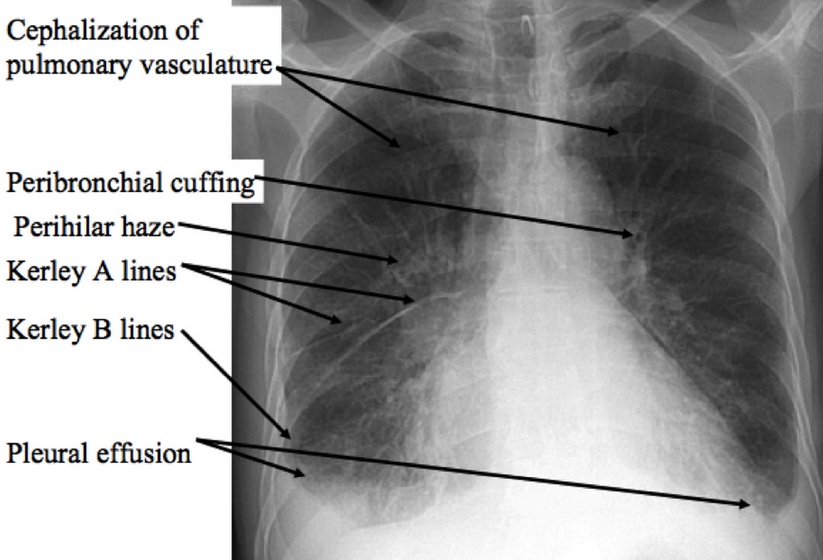

Chest x-ray findings include:

- Kerley B lines (thin pulmonary opacities caused by fluid in the interstitium of the lung)

- Enlarged cardiac silhouette

- Peribronchial cuffing (excess fluid in the small airway passages of the lung causes localized patches of atelectasis)

- Cephalization of the pulmonary vasculature (antigravitational redistribution of the pulmonary blood flow due in part to increased pulmonary vascular resistance and pulmonary hypertension)